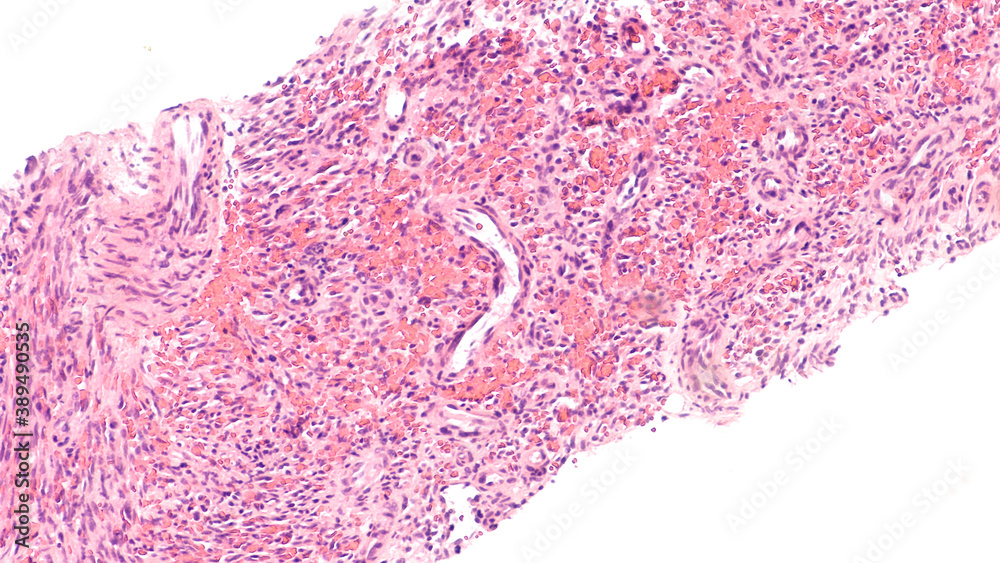

From www.alamy.com

Kaposi's Light micrograph of a section through part of the Kaposi Sarcoma Caused By Virus what causes kaposi’s sarcoma? Most people infected with this virus don't get kaposi sarcoma. But certain people who get this virus are more likely to develop one of the types of kaposi sarcoma: Kaposi sarcoma is a type of cancer that forms in the lining of blood vessels and lymph vessels. kaposi's sarcoma (ks) is an angioproliferative disease,. Kaposi Sarcoma Caused By Virus.

From stock.adobe.com

Kaposi's is a type of cancer of blood vessels caused by a virus Kaposi Sarcoma Caused By Virus kaposi's sarcoma (ks) is an angioproliferative disease, with a viral etiology and a multifactorial pathogenesis. Most people infected with this virus don't get kaposi sarcoma. It affects people with weakened immune systems who also carry the rare virus. kaposi’s sarcoma is caused by a virus called human herpes virus 8 (hhv8). kaposi sarcoma (kaposi’s sarcoma) is a. Kaposi Sarcoma Caused By Virus.